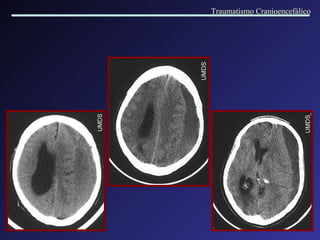

Lesão Axonal Difusa A lesão axonal difusa é mais frequentemente observada nas interfaces de tecidos com diferentes densidades. Os locais de acometimento mais comuns são: região cortico-subcortical nas regiões frontal e t emporal , corpo caloso,  fornix,  tronco cerebral, núcleos da base,  c á psul a interna. A RM é muito mais sensível na detecção destas lesões. Traumatismo Cranioencefálico

Lesão Axonal Difusa Traumatismo Cranioencefálico

Traumatismo Cranioencefálico